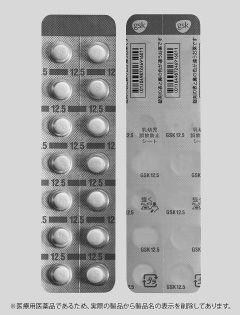

ノルバスク つたわるフォント で誤飲 取り違えを防止 ニュース

わたしたちの工夫 製剤 表示 包装工夫 第一三共エスファ株式会社